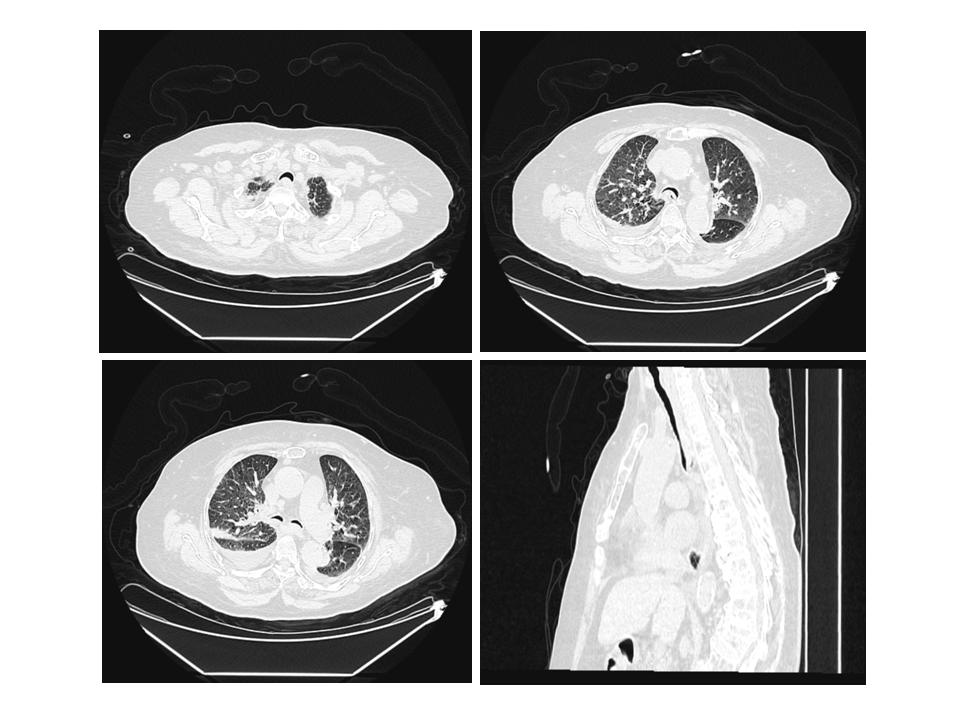

第一次就诊(2020年12月24日):因“阵发性胸闷气促2个月余,加重2 h”呼叫120送来本院就诊。患者近2个月内胸闷气促反复发作,活动后加剧。120到达现场时患者症状已好转。查体:神志清,血压165/92 mmHg(1 mmHg=0.133 kPa),脉搏血氧饱和度93%,呼吸23次/min。肥胖体型,面色无发绀,双肺呼吸音减低,未闻及干湿啰音及哮鸣音。心率110次/min,律规整。急查血常规:白细胞7.77×109/L,中性粒细胞百分比65.6%,床边肌钙蛋白Ⅰ 0.01 ng/mL,高敏肌钙蛋白T 20.4 pg/mL,血钾3.9 mmol/L,血钠132.6 mmol/L,血肌酐89 μ mol/L,血糖7.6 mmol/L。血气分析:pH 7.382,PaO2 68 mmHg,PaCO2 55 mmHg。心电图示:窦性心律,偶发室早。胸部CT平扫(图 1)示:(1)气管、主支气管及其分支退变,气管及双侧主支气管塌陷;(2)双肺慢性支气管炎,双肺多发间质性炎症,双侧胸腔少量积液;(3)左肺上叶前段实性结节,增殖灶可能。右肺上叶尖段及左肺下叶外基底段钙化灶;(4)纵隔及右肺门数枚淋巴结,部分增大。考虑慢性阻塞性肺疾病急性加重期,给予布地奈德雾化吸入、抗感染、平喘对症处理。8 h后患者症状缓解,自行出院。

|

| 气管及左右主支气管横截面呈新月型改变,膜部向管腔内凸出,气管下段管腔狭窄 > 50% 图 1 患者首次就诊(2020-12-24)胸部CT平扫及三维重建图 |

|

|